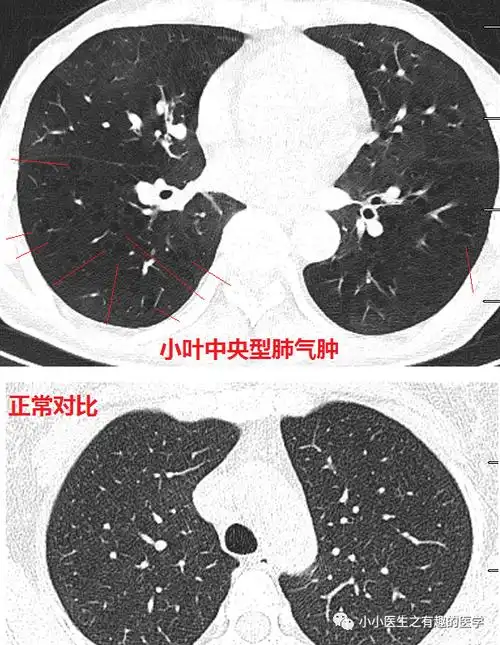

肺气肿ct典型图谱,一学就会_医学界-助力医生临床决策和职业成长